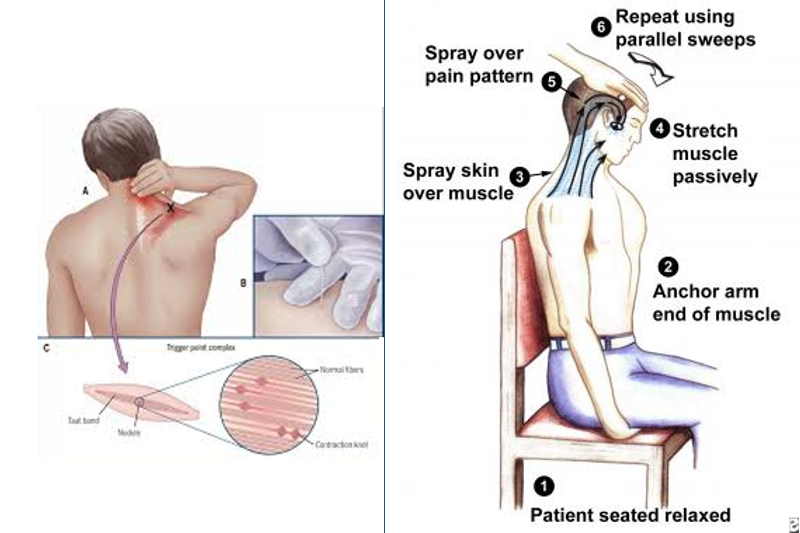

BACKGROUND Pain attributed to muscle and its surrounding fascia is termed myofascial pain, with cervical myofascial pain thought to occur following either overuse or trauma to the muscles that support the shoulders and neck. In the cervical spine, the muscles most often implicated in myofascial pain are the trapezius, levator scapulae, rhomboids, supraspinatus, and infraspinatus. […]